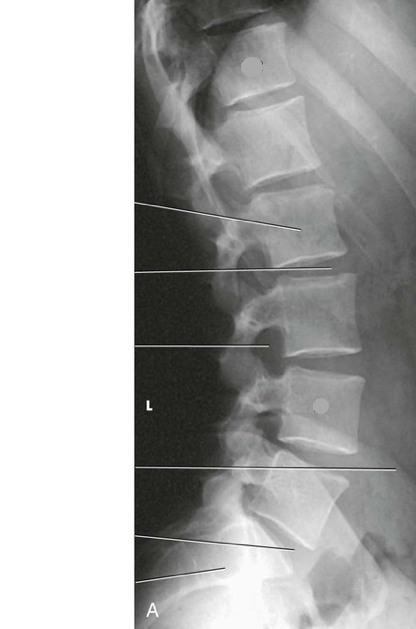

Question

Label the image

f6fa68f5-c033-406c-8af9-d78035e7a51c (image/png)

Answer

T12

L4

body

intervertebral disk space

intervertebral foramen

iliac crest

sacrum